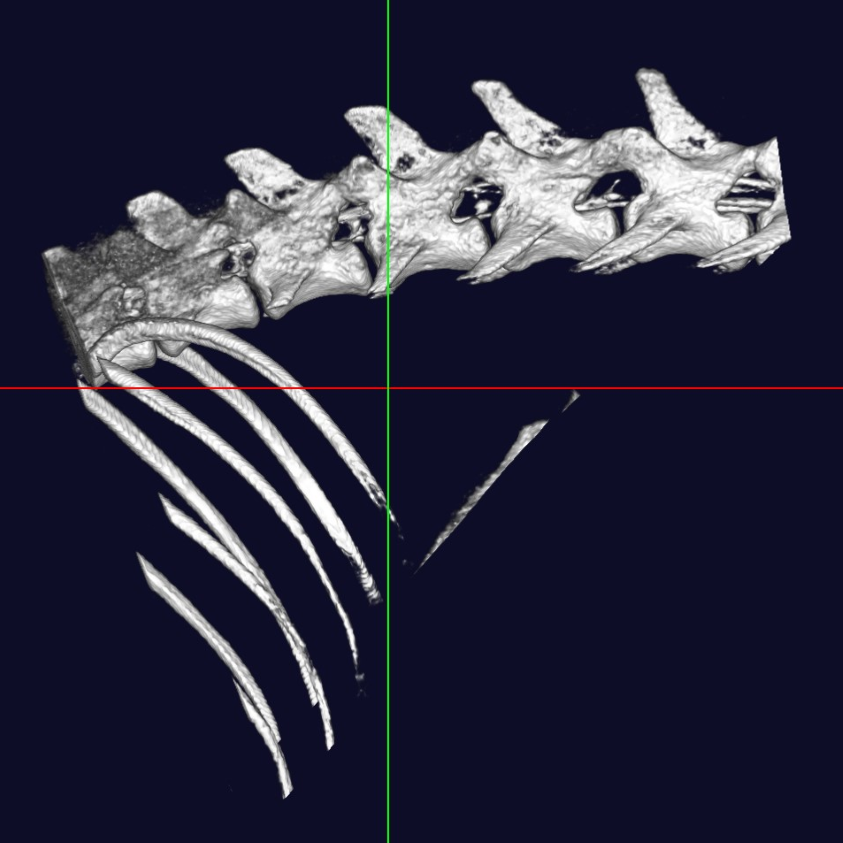

中・小型動物用3DマイクロCT

CTとはコンピューター断層撮影(Computed Tomography)の略で、X線を用いて身体の横断像(輪切り)を撮影することが出来ます。立体3D画像が得られるのも特徴で、主に骨格の異常や臓器系の異常部位、腫瘍性病変の把握に利用されます。

当院では「中・小型動物用3DマイクロCT」を導入しています。エキゾチックペットから猫・小型犬まで撮影可能です。

高画質で立体的に見ることで、レントゲンや超音波検査では分からない病態の診断や、構造が複雑な部位の細かい評価が可能です。

体の断層像に加え立体3D画像の作成が可能

事前に病変部位やその周囲の臓器との関係性を把握することで、より正確で安全な外科手術につながります。

また、飼い主様へお話しする際に、立体の3D画像のため病変のイメージがしやすくなります。

脊椎・脊髄・筋骨格

- 椎間板ヘルニア

- 骨折

- 脱臼

犬 椎間板ヘルニア